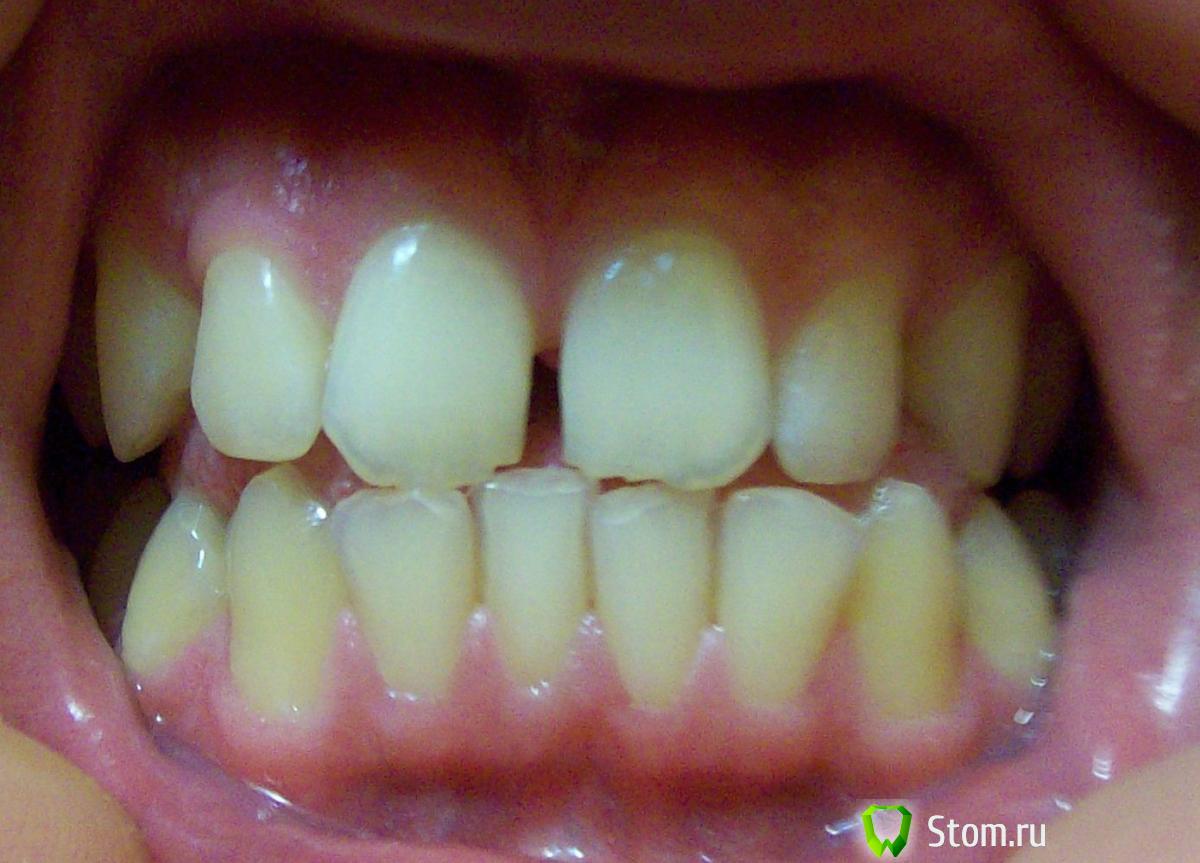

Здравсвуйте. Мне 23 года. Наконец-то руки добрались до кривых зубов. Цель была выпрямить зубы, убрать тремы, ну и заодно выпрямить прикус. Ортодонт на приеме сказал, что прикус у меня ужасный, что из-за него у меня впоследствии (лет через 10) будут большие проблемы с парадонтом, которые уже начались сейчас судя по снимку. Теперь меня забеспокила уже другая проблема. Два центральных нижних зуба у меня действительно немного шатаются уже сейчас. Действительно ли у меня настолько ужасный прикус, что из-за него через несколько лет зубы начнут еще больше шататься? Или же дело вовсе не в прикусе? И прокомментируйте пожалуйста парадонт на снимках тоже. Спасибо.

Основная нагрузка при функции приходится на фронтальные зубы, отюда подвижность и стираемость. Возможные проблемы с пародонтом могут быть связаны именно с неправильной нагрузкой. Правильное ортодонтическое лечение поможет решить вашу проблему, неправильное - ухудшит.

И еще скажите пожалуйста - прикус действительно ужасный? По мне так с таким прикусом минимум процентов 20 людей. И по деснам на снимке, если можно, комментарий пожалуйста.